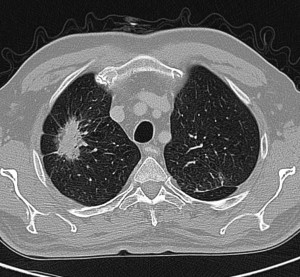

КТ грудной полости позволяет выявить воспалительные, сосудистые или опухолевые изменения в легких и средостении. На изображениях отчетливо видна структура легочной ткани, бронхов, лимфатических узлов и сосудов.